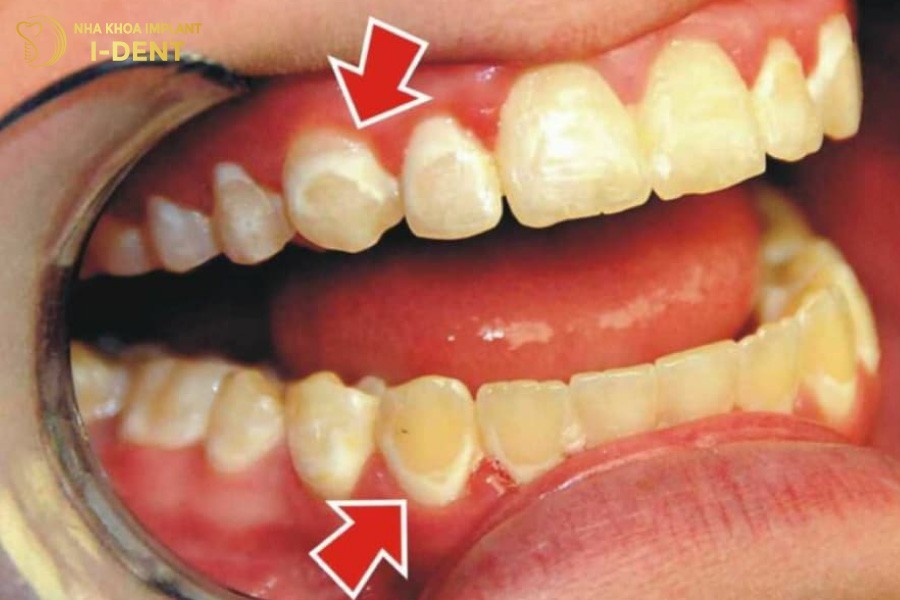

- Sâu chân răng (Root decay)

Sâu chân răng xảy ra trên bề mặt răng và phổ biến ở người lớn tuổi, đặc biệt là người có bệnh về nướu. Khi nướu tụt xuống, các mô xung quanh răng thấp đi khiến chân răng bị lộ ra và dễ bị tấn công bởi axit và vi khuẩn.